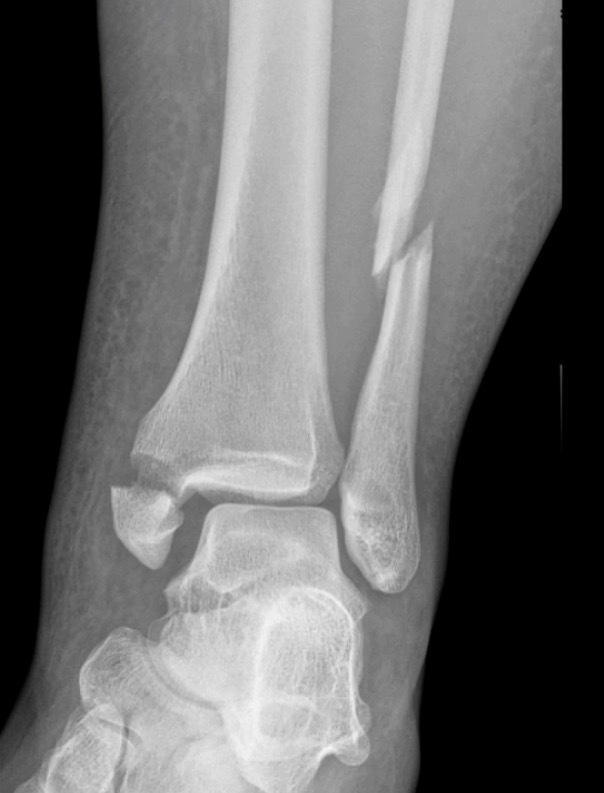

Our Randomized Controlled Trial specifically excluded those, because when I was a resident, syndesmosis injury was kept non-weight-bearing for three months, that was the standard (three months in a cast). Unfortunately, the treatment is sometimes worse than the disease. There is much controversy in terms of weight bearing for syndesmosis injuries, and not as much evidence on this specific injury compared to previously discussed ankle fractures. Figure 7 is a type of fracture we’re referring to: After you fix it, what do you do next?

A small RCT (Khaleel M, et al. Foot Ankle Orthop. 2024;9(4)) was conducted assessing syndesmosis injuries comparing early versus delayed weight-bearing. They had a relatively small sample size: only 16 patients in one group, 23 in the other group, but they did show that there was potential improvement in range of motion with the early group, and there was no catastrophic failure. This raises an interesting question: “can we allow early weightbearing after syndesmosis fixation?”, and we need more studies on this specific topic.